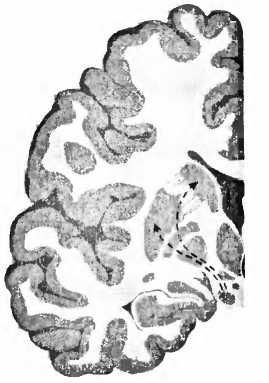

NCSN норма

болезнь Паркинсона

Рис. 23. При болезни Паркинсона пигментированные черным клетки, производящие дофамин в черной субстанции (SN), умирают и уже больше не могут управлять моторной областью — полосатым телом стриатумом (Р — putamen, скорлупа; NC — nucleus caudatus, хвостатое ядро).